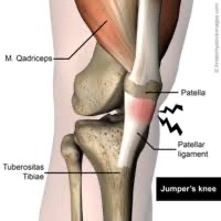

Infrapatellar Tendinitis or “Jumpers Knee” is a common form of AKP. The Infrapatellar Tendon (below the patella) is considered “ligamentous” by some, as it connects bone to bone (patella to tibia).

Infrapatellar injuries can be chronic and very frustrating. As the radiographic diagram above indicates, the infrapatellar tendon comes under “stretch” load as the knee flexes. When a vigorous quadriceps contraction occurs, stretch load is greatly accentuated by muscle induced tension as the quad acts on the tibia. Forces are particularly high in the tendon during  “rapid load storing and release” activities (i.e. plyometrics). Eccentric activities can have either an injurious or reparative affect based on dosage. A review of a previous Nordic Solutions post entitled, “The Role of Eccentric Exercise in Early Season Training” is recommended.

An athlete with “Jumper`s Knee” will typically limp during running, or bounding activities. When skiing, the athlete will demonstrate a “stiff” knee and hip approach to dynamic loading of the limb. Often the region “feels better” once “warmed up” but then hurts again later in the work out and at rest. The involved region will likely be tender but will not show signs of swelling (effusion) as the infrapatellar tendon is external to the knee articulation proper, making accumulation of inflammatory fluids unlikely. Athletes typically complain “stiffness” and pain after sitting for a time (i.e. long car rides) or on stairs, particularly descending.